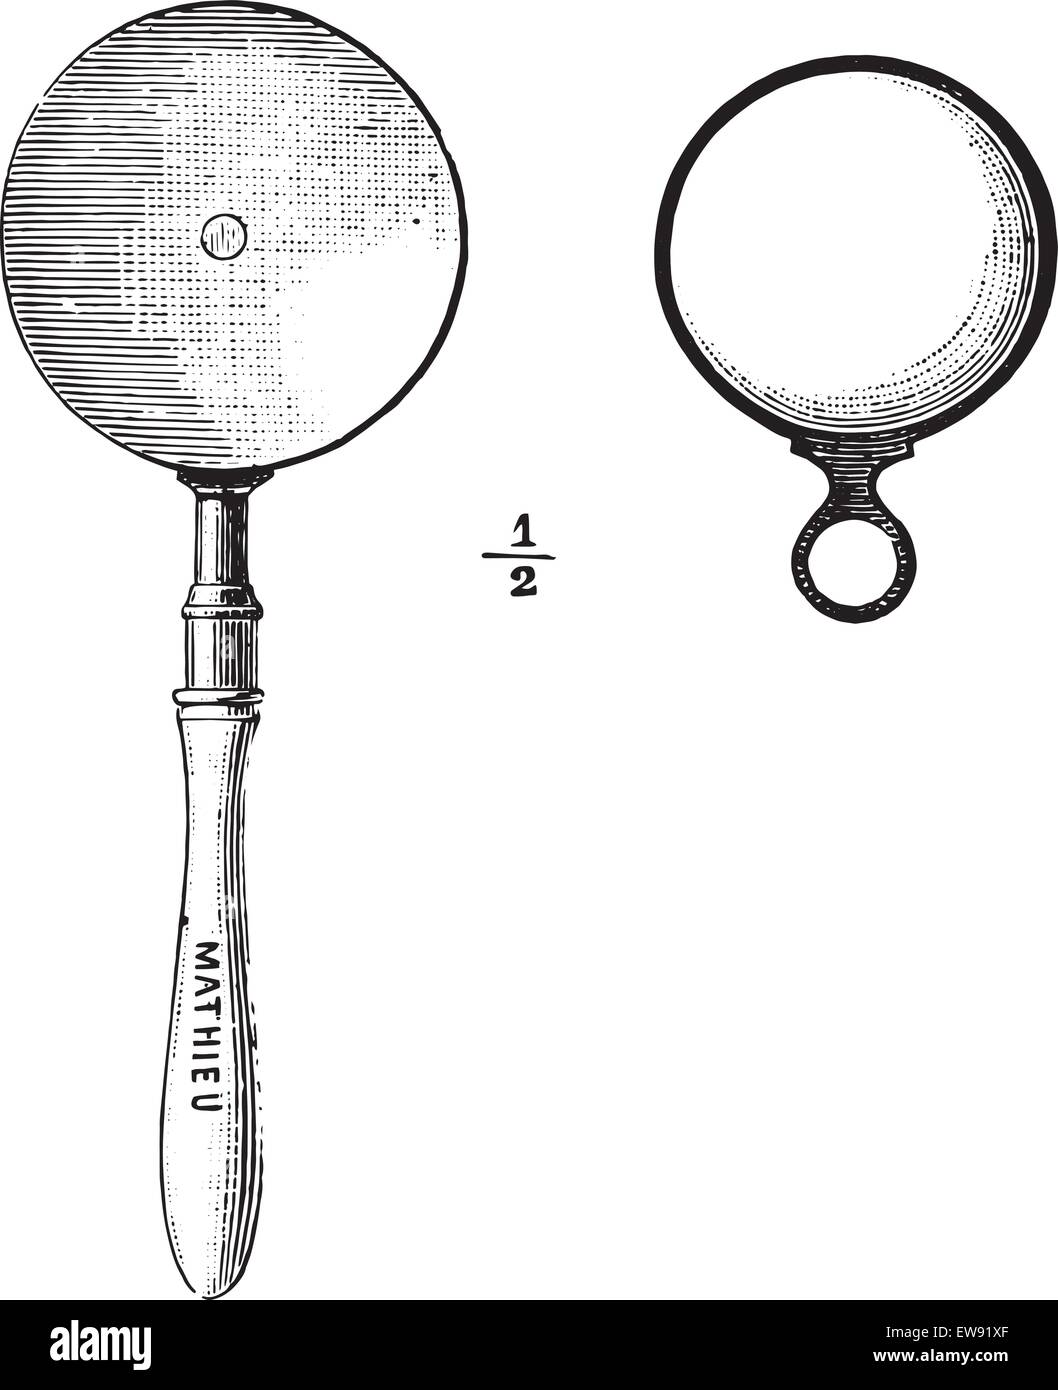

Ophthalmoscope, vintage engraved illustration. Usual Medicine Dictionary - Paul Labarthe - 1885. Stock Vectorhttps://www.alamy.com/image-license-details/?v=1https://www.alamy.com/stock-photo-ophthalmoscope-vintage-engraved-illustration-usual-medicine-dictionary-84419385.html

Ophthalmoscope, vintage engraved illustration. Usual Medicine Dictionary - Paul Labarthe - 1885. Stock Vectorhttps://www.alamy.com/image-license-details/?v=1https://www.alamy.com/stock-photo-ophthalmoscope-vintage-engraved-illustration-usual-medicine-dictionary-84419385.htmlRFEW9HP1–Ophthalmoscope, vintage engraved illustration. Usual Medicine Dictionary - Paul Labarthe - 1885.

Ophthalmoscope, vintage engraved illustration. Usual Medicine Dictionary - Paul Labarthe - 1885. Stock Vectorhttps://www.alamy.com/image-license-details/?v=1https://www.alamy.com/stock-photo-ophthalmoscope-vintage-engraved-illustration-usual-medicine-dictionary-84406967.html

Ophthalmoscope, vintage engraved illustration. Usual Medicine Dictionary - Paul Labarthe - 1885. Stock Vectorhttps://www.alamy.com/image-license-details/?v=1https://www.alamy.com/stock-photo-ophthalmoscope-vintage-engraved-illustration-usual-medicine-dictionary-84406967.htmlRFEW91XF–Ophthalmoscope, vintage engraved illustration. Usual Medicine Dictionary - Paul Labarthe - 1885.